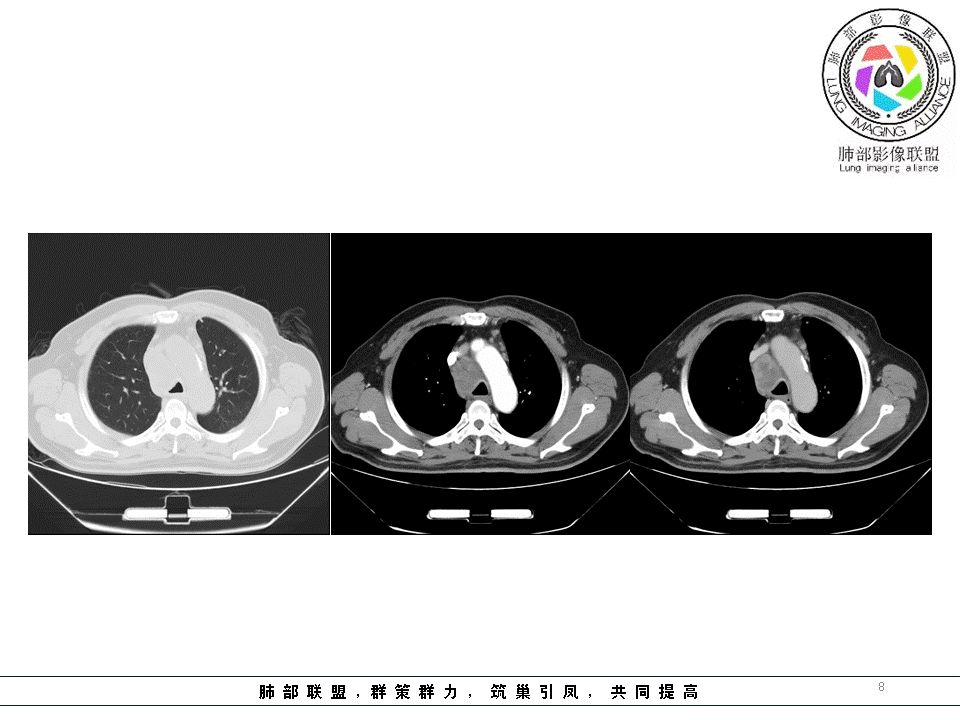

南边:但是我们看纵隔就多发的肿大淋巴结,部分融合成团。

南边:而且这些淋巴结,有些直接主要是压迫支气管壁,但是有些是突入到支气管腔内的。可惜我截的图发不上来。就左上舌段,支气管壁明显的增厚。有些明显腔内突的一个结节的,但是远的没有阻塞的特点。南边:增强以后呢,这个病灶明显强化,部分的似乎有环形强化的迹象,但不是很典型。

我们看这个主支气管的层面,主支气管明显受压,有变形的,但是软骨是没有突破的。

南边:那也就是说,这个纵隔淋巴结,它是没有影响到我们主支气管内部去的,周围有,可惜的膜部的增厚,我总心里不踏实,后面因为食道贴在一起啦。 因此这些淋巴结在主支气管层面是没有影响的。

结果:肺腺癌并纵膈淋巴结转移